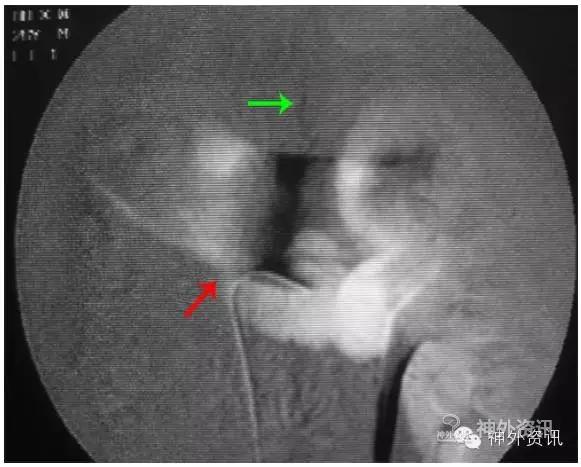

②选择性肾静脉造影,注入非离子造影剂(7ml/s、总剂量10ml),使肾静脉显影,了解肾静脉有无狭窄、闭塞,或向下腔静脉回流障碍而经肾椎静脉干返流向椎管内静脉,引起椎管内静脉高压综合征[8],导致脊髓功能受损。对动脉造影阴性,而又不能排除脊髓静脉高压综合征者,应做选择性左肾动脉造影,了解左肾静脉向下腔静脉回流有无障碍(图13)。

图13: 左肾静脉狭窄致脊髓静脉高压综合征,红色↑示肾静脉狭窄,绿色↑示向肾椎静脉回流。